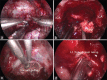

Giant cell reparative granuloma (GCRG) is a benign nonneoplastic granulomatous lesion and is rare in the cranial bone. We present a pediatric case of this lesion arising from the condyle and lower clivus. A 9-year-old girl presented with slowly progressive hoarseness and dysphagia. She showed left glossopharyngeal, vagus, and hypoglossal nerve palsy. An osteolytic lesion around the lower clivus and condyle joint was accompanied by deformation of the craniovertebral junction. An endoscopic endonasal approach was used to decompress the cranial nerve and confirm the pathological finding. The lesion around the condyle was not resected to preserve occipito-cervical stability. The residual lesion has been observed carefully for 6 months, and regrowth has not occurred. GCRG is a rare granulomatous lesion in the cranial bone. This case is the first report of a pediatric clival GCRG. Treating pediatric GCRG may be helpful.